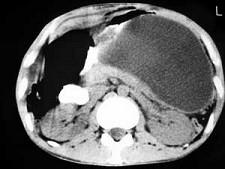

问题 男,33岁,腹部外伤后两月余,腹部疼痛,行CT扫描所见如图,最可能的诊断是 ( )

选项 A、畸胎瘤 B、腹腔包裹性积血 C、慢性胰腺炎 D、胰腺创伤性假性囊肿 E、急性胰腺炎

答案 D